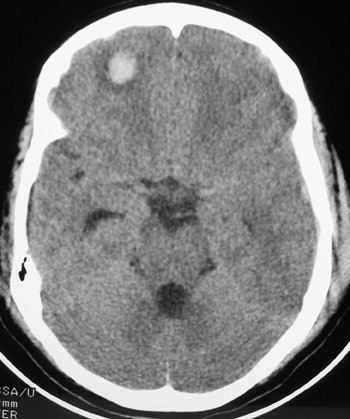

![]() |

| The image above illustrates a right frontal lobe parenchymal hemorrhagic contusion. This represents bleeding in the brain and is commonly seen following blunt trauma to the head. |